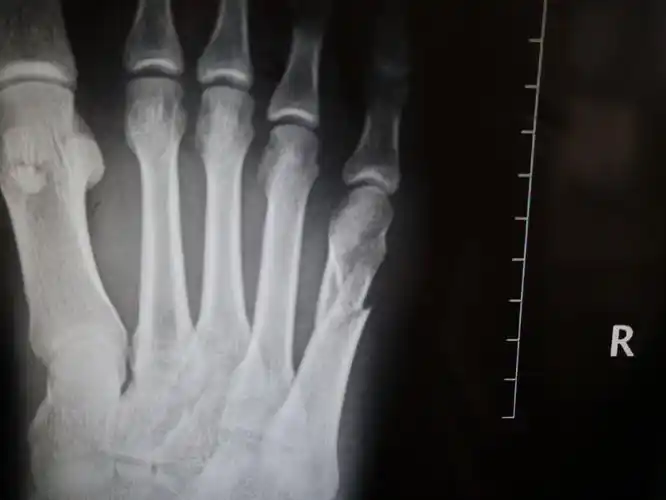

右脚第二第四跖骨(脚趾骨)骨折0101